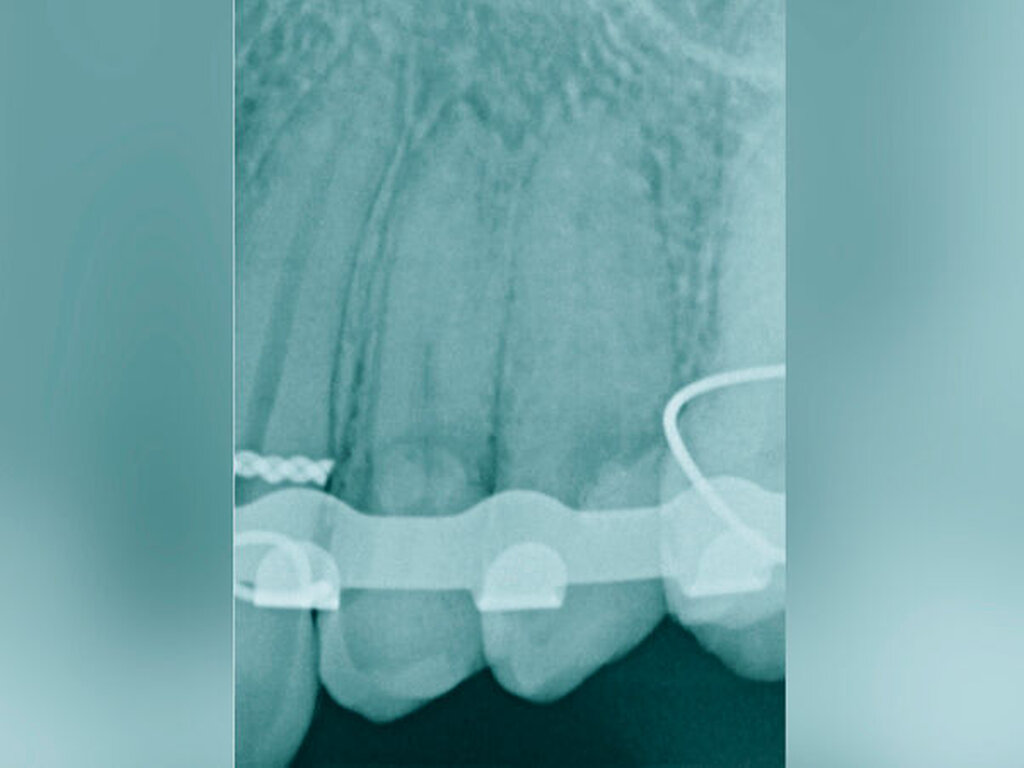

Eine sehr gewebeschonende, jedoch zeitlich aufwendigere Technik zur Generierung eines Ferrule-Effekts bei tief zerstörten Zähnen ist die kieferorthopädische Extrusion [Bondemark et al., 1997; Brandt, 2016; Krastl, 2004; Carvalho et al., 2006; Hergt und Christofzik, 2017; Mehl et al., 2017; Wirsching, 2011]. Diese Technik ist prädestiniert für die ästhetische Zone, da hier im Gegensatz zu anderen invasiveren Techniken kein Gewebeverlust auftritt. Vielmehr kann durch den langsamen Extrusionszug vermittelt über den parodontalen Faserapparat eine Migration des Hart- und Weichgewebes (falls gewünscht) induziert werden. Wird während der Extrusionsphase das parodontale Ligament regelmäßig durchtrennt, findet folglich keine Gewebsmigration statt [Carvalho et al., 2006].

Als Hilfsmittel, die die Zugkräfte auf die betroffenen tief zerstörten Zähne übertragen können, eignen sich spezielle Magnet- oder Gummizug-Systeme (zum Beispiel Neodym-Scheibenmagnete; TMC Extrusion, Komet GmbH) (Abbildungen 12 und 13). Bei den Magnetsystemen ist in der Regel ein Abstand von 0,5 bis 2 mm zum Kontermagneten über einen Abstandshalter nötig. Der Kontermagnet wird in einer Tiefziehschiene oder in ein entsprechendes Methacrylatprovisorium mit Abstützung an den Nachbarzähnen einpolymerisiert. Die Zugkraft beeinflusst die Art der Extrusion. Kräfte mit circa 0,3 N verursachen eine verzögerte Extrusion um etwa 1 mm pro Woche. Die forcierte Extrusion erfordert mindestens 0,5 N, um eine Extrusion von mehr als 1 mm pro Woche zu bewirken [Krastl, 2004].

Die Extrusionzeit beträgt zumeist vier bis acht Wochen, wobei eine initiale, meist länger dauernde Phase der Zahnlockerung keine merkliche Bewegung verursacht und in einer sekundären kürzeren Phase von wenigen Tagen die Extrusionsbewegung stattfindet. Eine teils langwierige Retentionsphase von mindestens vier bis acht Wochen schließt sich an. Vorteilhaft sind das intakte Weichgewebe und die äußerst einfache Hygienefähigkeit.